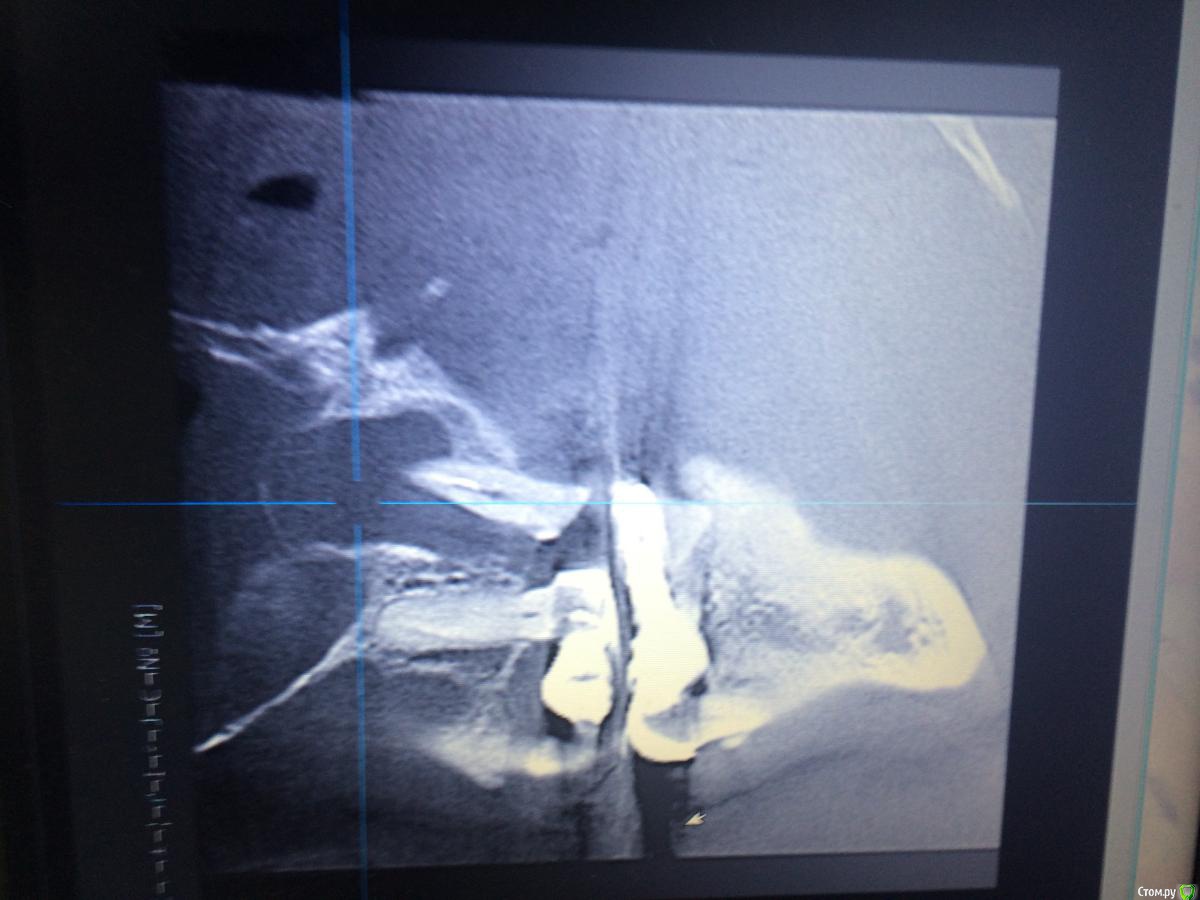

Shargik Опубликовано 23 октября, 2015 Поделиться Опубликовано 23 октября, 2015 Господа эндодонтисты, вот Вам такой случай.. Как думаете, стоит с ним повоевать, или сразу в плевашку? Беспокоит выбухание на небе и свищ с непрекращающимся гноетечением, каналы все проходимы, вот думаю, что с ним делать. Кто прилагается.. Ссылка на комментарий

Shargik Опубликовано 23 октября, 2015 Автор Поделиться Опубликовано 23 октября, 2015 Зуб 26, на небном корне обширный процесс. С небной стороны кости нет от слова совсем. В том то и дело, что пациент не сильно платёжеспособен, думается мне попробовать полечить, авось косточки хоть чуть вырастет, или думаете, это с мельницами бодаться.. Ссылка на комментарий